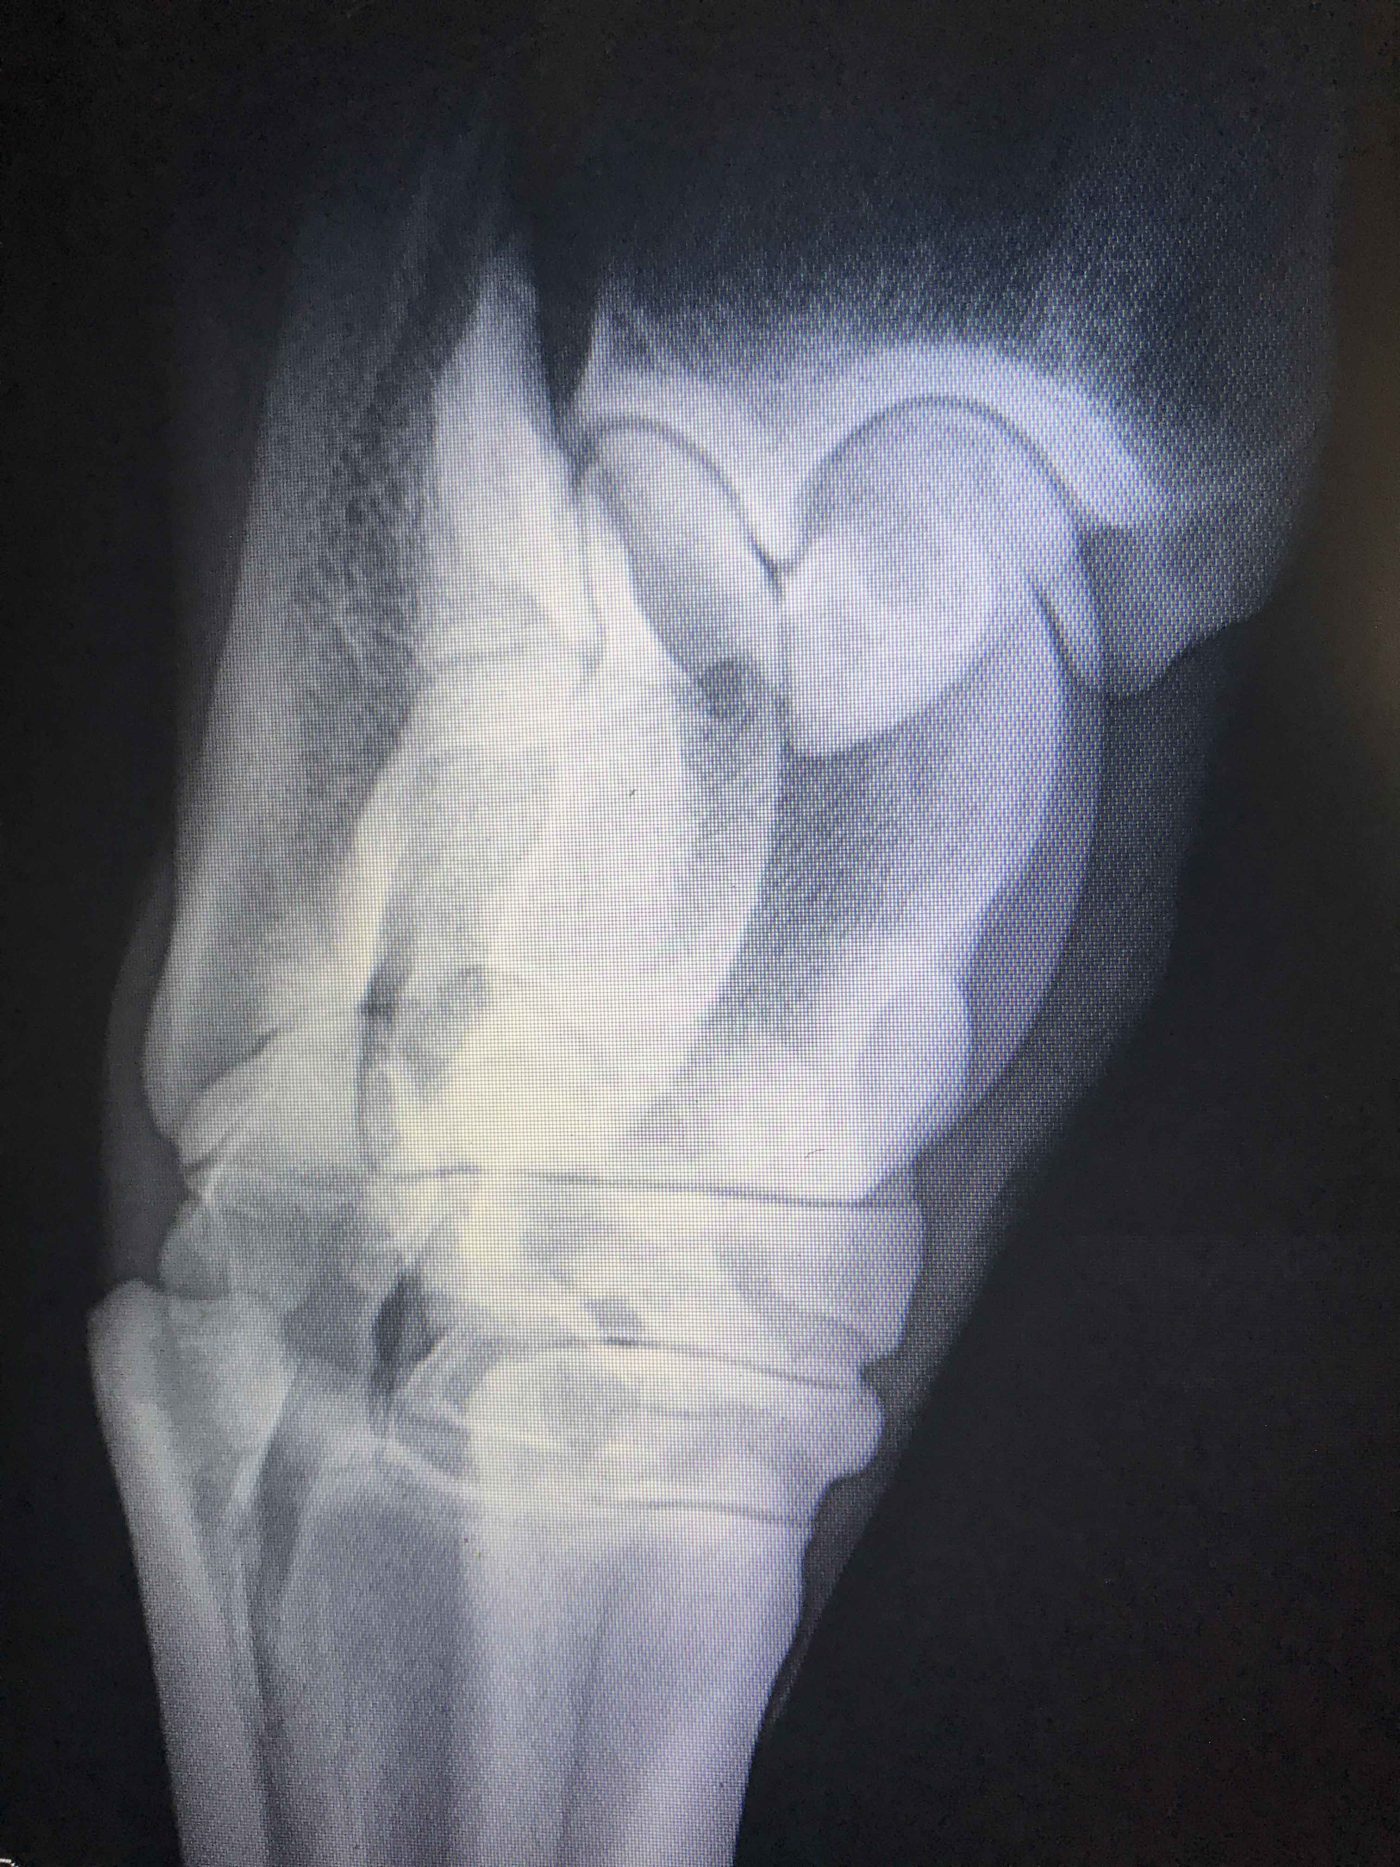

Frac Hock 2 Eastern Equine Associates Eastern Equine Associates Horse Hock Fused Find out how to prevent and treat. Hock fusion is when severe osteoarthritis causes the lower hock joints to become immobile and fused. Learn about the causes and symptoms of hock problems in horses, such as djd, bone spavin and osteoarthritis. For some affected horses, this might be a good thing. Learn how to recognize the signs of hock fusion,. Horse Hock Fused.

Bone Spavin Horse Hock Fused 3 types of fusing hock processes. With that in mind, there are three. Fusion, or arthrodesis, is the body’s. Hock fusion is when severe osteoarthritis causes the lower hock joints to become immobile and fused. For some affected horses, this might be a good thing. Osteoarthritis in horses’ hocks can lead to joint fusion. Hock arthritis is a common condition. Horse Hock Fused.

Spavin fused hocks Veterinary Services Horse Hock Fused Fusion, or arthrodesis, is the body’s. Hock fusion is when severe osteoarthritis causes the lower hock joints to become immobile and fused. With that in mind, there are three. Find out how to prevent and treat. Hock fusion is a surgical or natural process that immobilizes the lower hock joints to relieve osteoarthritis pain. Learn about the causes and symptoms. Horse Hock Fused.